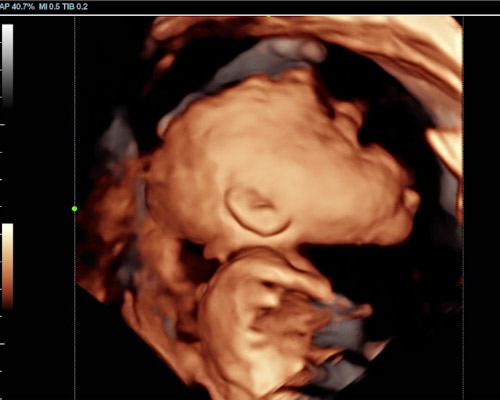

A 3D scan creates detailed still images showing your baby’s features, while a 4D baby scan allows you to see those images in motion. You may notice gentle movements, stretches, or even small expressions, which can make the experience feel much more real.

With a 4D baby ultrasound Huddersfield, this advanced imaging allows parents to see their baby in a way that feels closer to a photograph than a traditional scan.

- Clearer facial detail - improved definition and shape

- Live movement visibility - See actions as they happen

Our Scans